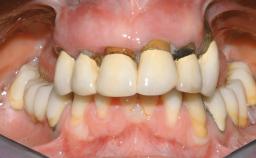

A 63-year-old male patient was referred for a consultation and treatment of partial edentulism in the maxilla. The patient presented with residual anterior teeth and declined a partial removable prosthesis. He reported that the maxillary posterior teeth had been extracted due to mobility and periodontal disease two months before the consultation. The patient’s chief complaint was that his residual maxillary teeth were mobile and that he was unable to chew. The patient’s desire was a stable and comfortable fixed maxillary rehabilitation. The patient was a light smoker (fewer than 10 cigarettes/ day), and his medical history was without significant findings. He was not on any regular medication at the time of consultation. The extraoral examination revealed a normal physiognomy with a correct distribution of the facial thirds. The patient presented a low lip line, and the transition line between teeth and soft tissues was not exposed during a forced smile.

Lip Line No exposure of papillae Exposure of papillae Full exposure of mucosa margin

Periodontal Phenotype Low-scalloped, thick Medium-scalloped, medium-thick High-scalloped, thin

Soft Tissue Anatomy Intact Defective

Periodontal Status History of periodontitis or genetic predisposition